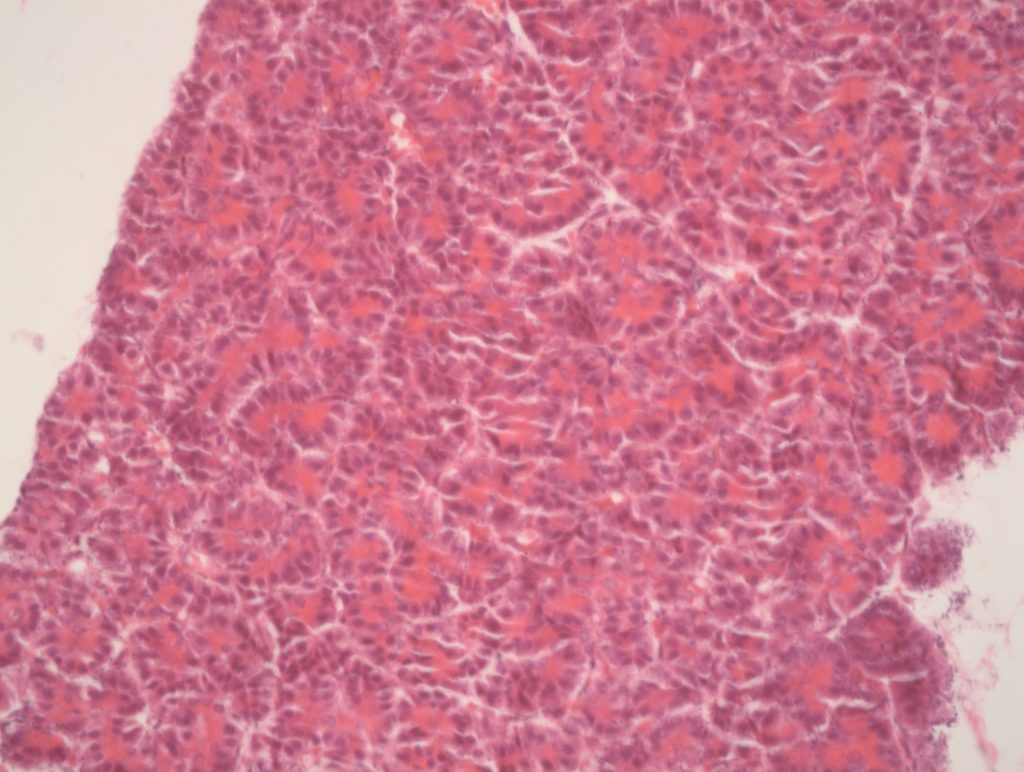

Pâncreas - Aumento 10x

Mostra as glândulas tubuloalveolares e o tecido fibromuscular que forma os septos entre o tecido glandular